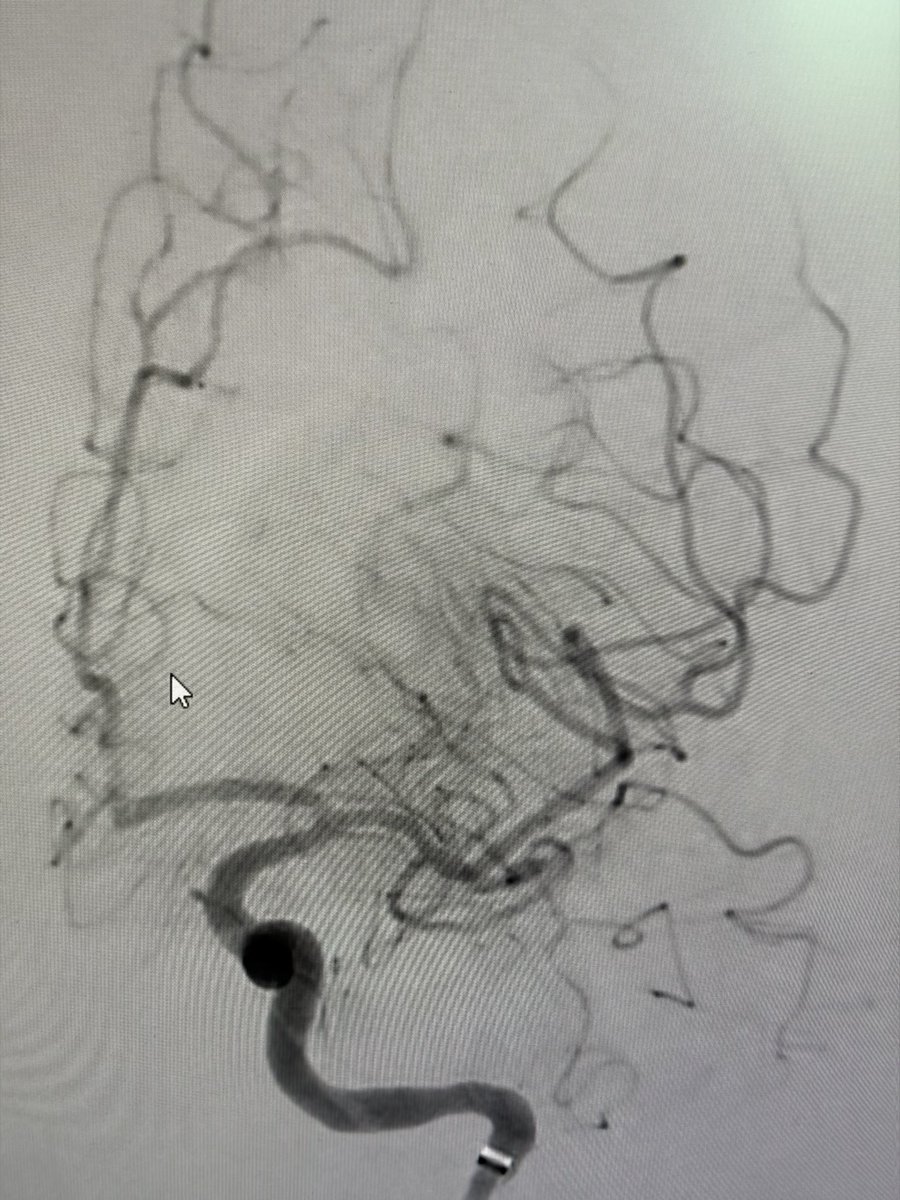

Two weeks ago, a 54-year-old patient recovering from open-heart surgery (CABG) suffered a major stroke. • Symptoms: Sudden inability to speak + right-side paralysis. • Action: Immediate Mechanical Thrombectomy to remove the brain clot.

Manish Kumar Yadav tweet mediaManish Kumar Yadav tweet mediaManish Kumar Yadav tweet mediaManish Kumar Yadav tweet media